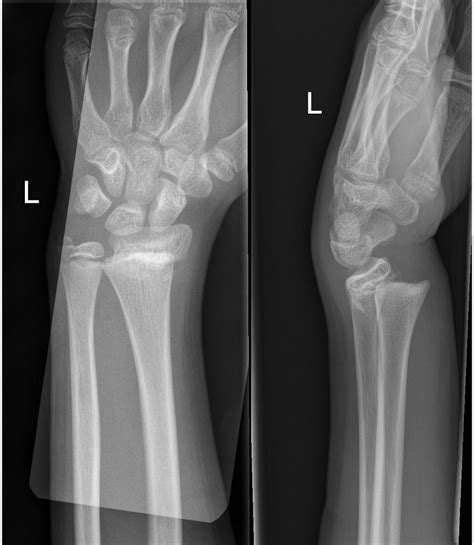

Distal radius fractures programme online course:

Types i to v as described by robert b salter and w robert harris in 1963,2 and the rarer types vi to ix which have been added subsequently:4. M = metaphyseal involvement, e = epiphyseal involvement, me = metaphyseal and epiphyseal involvement. Related online courses on physioplus. However, only 5 degrees of angulation. It is a common injury found in children, occurring in 15% of childhood long bone fractures. Distal radius fractures programme online course: These fractures (radiographs of which are presented below) are categorized according to the involvement of the physis, metaphysis, and epiphysis. Management of distal radius fractures programme complete overview. There are 5 types of salter harris fractures, learn them here.learn more at. The higher the classification, the higher the likelihood of growth abnormalities. However, only 5 degrees of … Rotational deformities after sh fractures are rarely reported in literature. Salter harris fractures are those which involve the growth plate of long bones. This type of fracture was first described in 1963 by robert b. Involves both the epiphyseal plate and the metaphysis. If physis fracture missed may lead to premature closure and bone growth arrest. Injuries to the extremities of children frequently involve the physis, partially because the ligaments and joint capsule can be 5 times stronger than the growth plate.1 about 15% of fractures of children involve the growth.